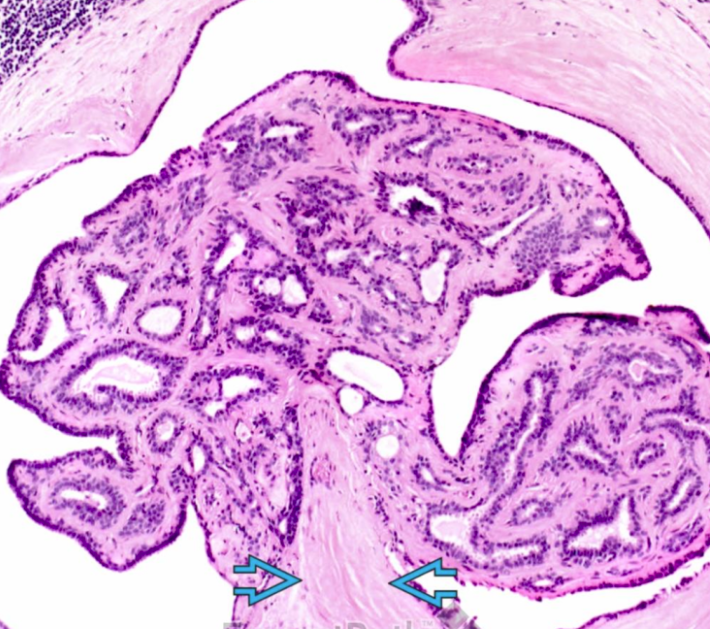

What type of pathology is indicated here?

Intraductal papilloma

Note the growth of the papilloma into the milk duct